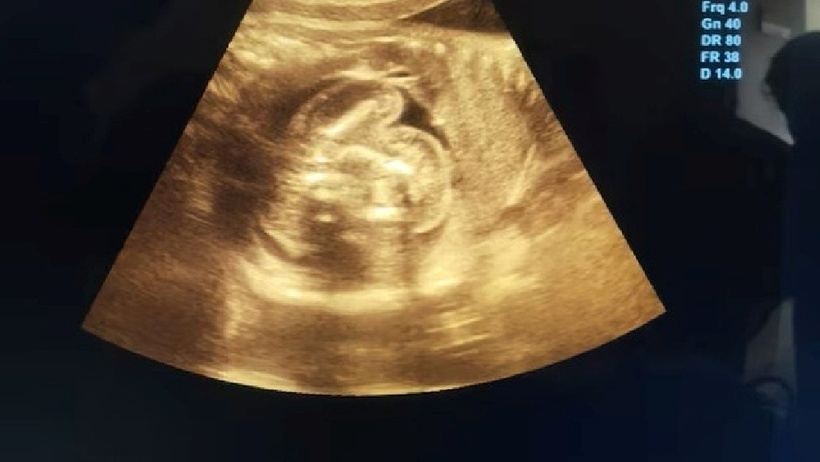

Kết quả siêu âm cho thấy, bên trong bụng bé là 2 bào thai chưa phát triển, nằm gọn trong 1 túi duy nhất.

Bên trong bụng bé là 2 bào thai chưa phát triển, nằm gọn trong 1 túi duy nhất. Ảnh: India Today.